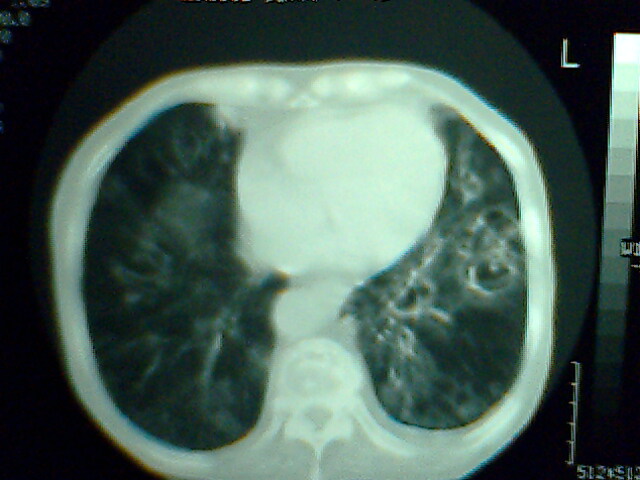

以上是2009-05-25的照片。

以下是引用hhx58在2009-9-11 19:48:00的发言:[br]有4个是心电监护的电极。[br]ct图片可见有肺气囊。但未拿到片上传。

以下是引用37度在2009-9-12 11:54:00的发言:[br][br] [br] 支气管扩张合并混合型感染 [br] [br]

以下是引用dyqct在2009-9-12 8:42:00的发言:[br]慢性支气管炎合并间质纤维化、肺气肿、支气管扩张、感染。建议ct进一步检查。

以下是引用黑白光影在2009-9-12 16:43:00的发言:[br]慢支并感染(霉菌?)